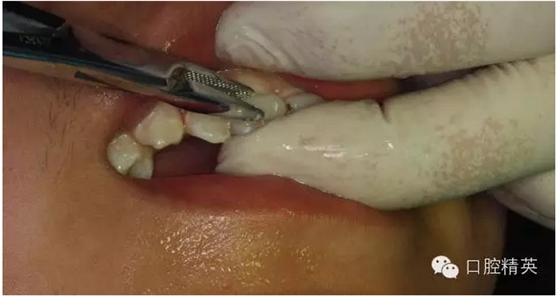

圖13.清理21牙槽窩

圖14.再植21離體牙

圖15.縫合初固定21